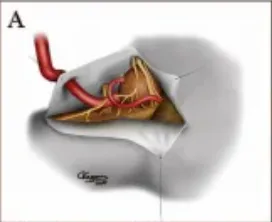

VA-PICA端端吻合术

INC巴特朗菲教授在其论文中详细描述了VA-PICA端端吻合术在一例VA-PICA复杂动脉瘤患者中的成功应用及技术要点。

(图A)VA直接进入大而厚的动脉瘤囊,PICA起源于动脉瘤囊VA复合体。动脉瘤壁因严重钙化而硬化,以致常规动脉瘤夹闭难以奏效。在这一阶段,我们决定进行VA-PICA吻合术。动脉瘤近端和远端PICA暂时夹闭,以避免动脉瘤逆行出血。

供体血管和受体血管在动脉瘤附近被切开,VA直切,PICA斜切45度,扩大血管末端直径。缝合前用肝素化生理盐水冲洗血管末端。

(图D)完成吻合术后,松开临时夹,精心控制吻合口,防止吻合口瘘,术中多普勒超声证实血管通畅。下一步是打开动脉瘤囊,取出囊内的大部分血栓性物质。在动脉瘤囊减压完成后,大部分动脉瘤壁完全切除。

在这个阶段,靠近椎动脉交界处的远端椎动脉变得可见,因此对远端椎动脉进行了额外的夹闭,使脊髓前动脉和小脑干穿支得以游离。部分附着于延髓和近端桥的动脉瘤囊被保留在适当位置,以避免操纵或损坏这些结构。在确认硬膜内止血后,在无需硬脑膜移植的情况下,进行了一次水密硬脑膜闭合术。